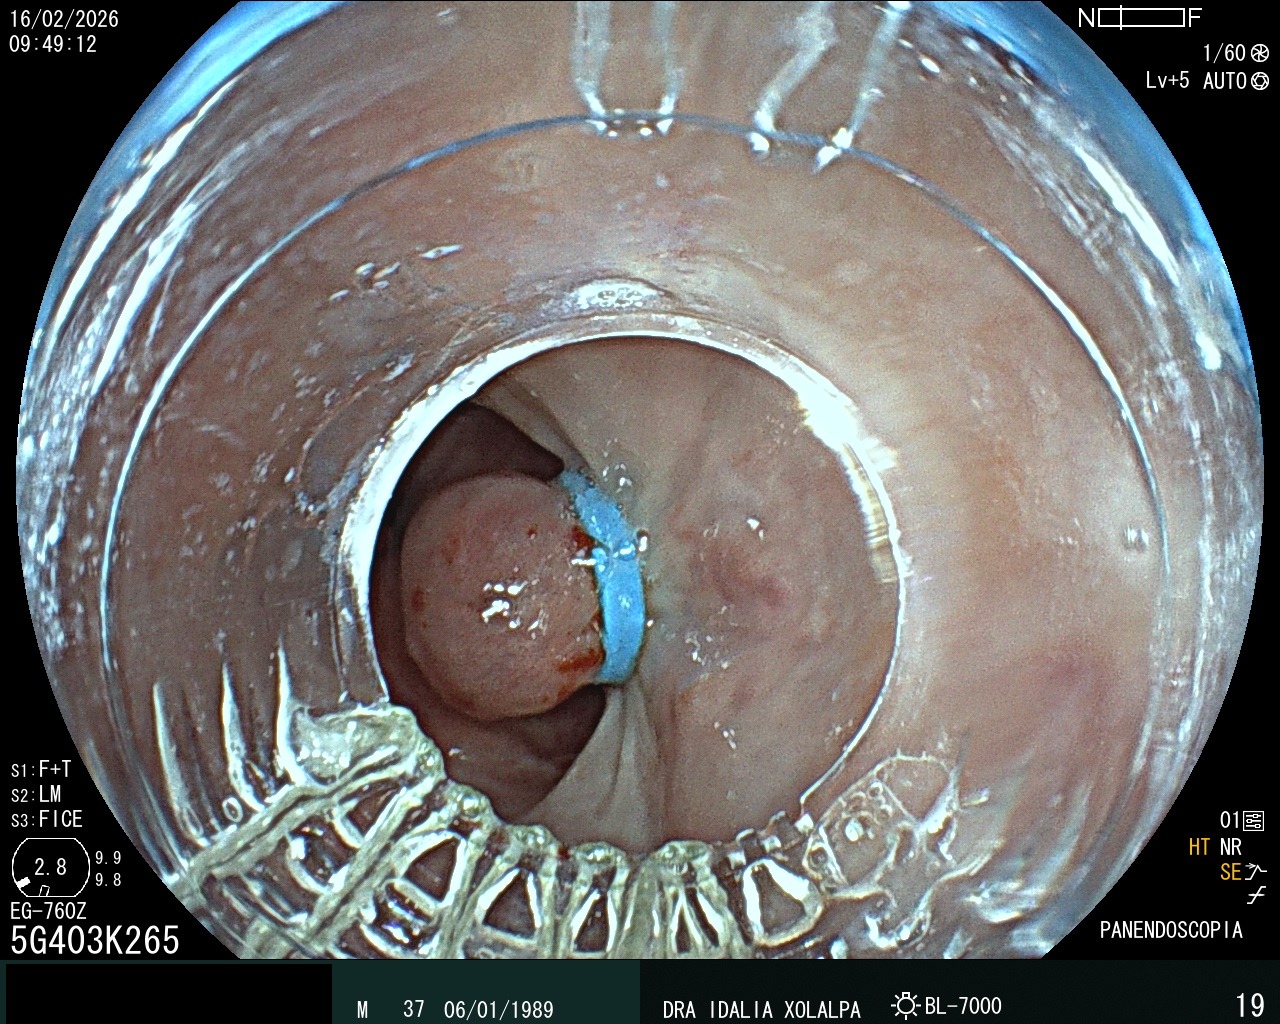

Ligadura de Várices

Tratamiento de várices esofágicas por endoscopia

Várices Esofágicas

Identificación de várices esofágicas